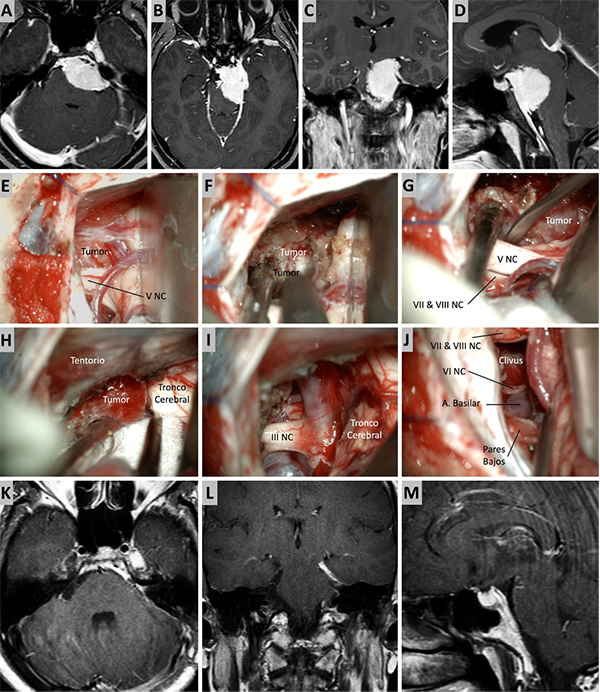

Figura 3. Caso ilustrativo #1. MRPC con implantación petroclival, extensión a la fosa media y compromiso de la incisura tentorial. Paciente con audición conservada. A. Corte axial sobre la región clival media. B. Corte axial sobre la región clival superior. Corte Coronal. D. Corte sagital donde se observa el efecto compresivo sobre el tallo cerebral. E-J. Se realizo un abordaje retrosigmoideo. K-N. Se muestra las imágenes en distintos cortes con el resultado quirúrgico. Residuo tumoral incipiente sobre la incisura tentorial.

Figura 4. Caso ilustrativo #2. MRPC con implantación petroclival, extensión a la fosa media y compromiso de la incisura tentorial. Paciente con audición conservada. A. Corte axial sobre la región clival media. B. Corte axial sobre la región clival superior. Corte Coronal. D. Corte sagital donde se observa el efecto compresivo sobre el tallo cerebral. E-J. Se realizo un abordaje retrosigmoideo. K-N. Se muestra las imágenes en distintos cortes con resección quirúrgica completa.